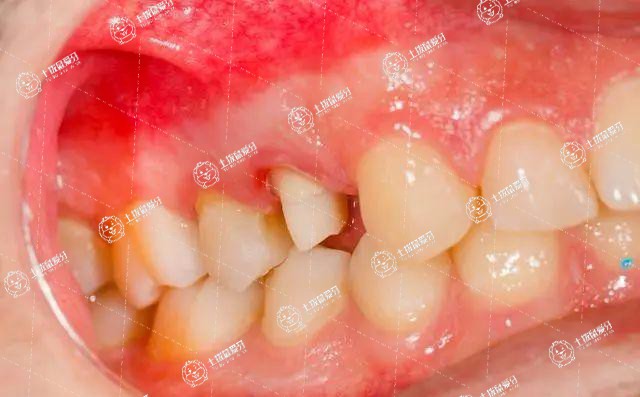

牙齒矯正牙齦腫痛需要及時(shí)到醫(yī)院復(fù)診。

通過口腔X光片檢查,判斷牙齦腫痛的原因,如果只是輕微紅腫,并不存在發(fā)炎,通常屬于牙齒矯正期間正常的反應(yīng),如果疼痛比較嚴(yán)重,也可以遵醫(yī)囑服用些止痛的藥物,或是通過調(diào)整牙齒矯正的力度來改善。

在確診是細(xì)菌感染發(fā)炎引起的腫痛時(shí),需要局部給藥來來緩解疼痛并結(jié)合口服消炎藥物治療。

如果是因?yàn)榭谇恍l(wèi)生不佳引起的牙齦炎,就需要加強(qiáng)口腔衛(wèi)生,使口腔保持清潔。